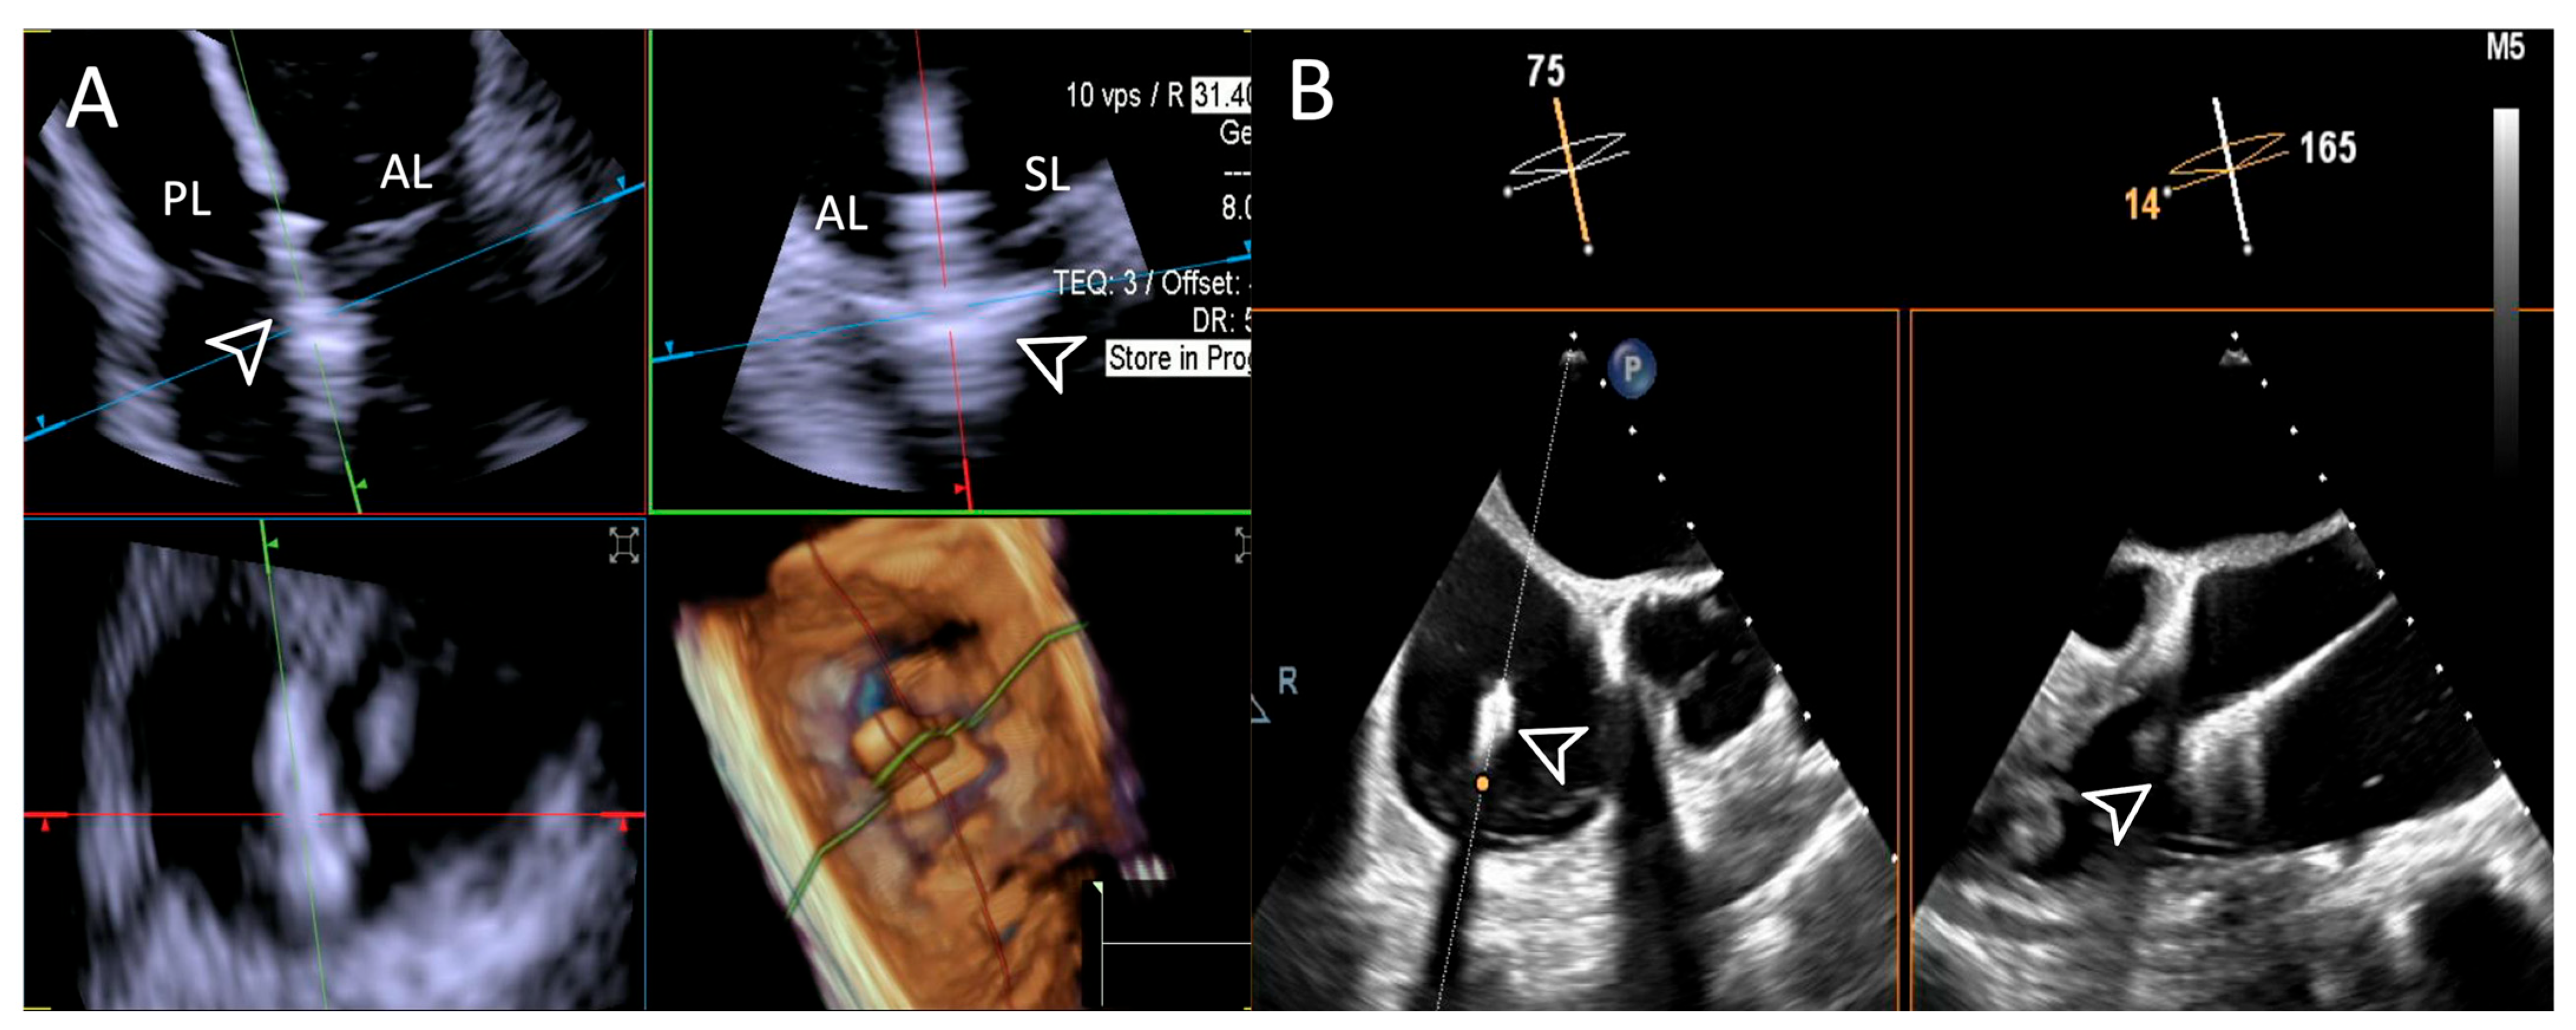

- Step number 3: steering and valve approach.

- Step number 4: ensuring perpendicularity and correct trajectory.